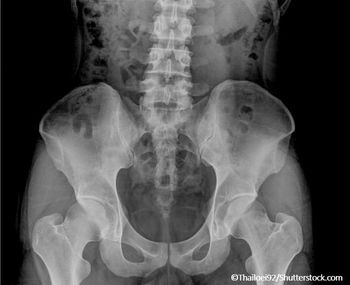

Patients with osteoporosis have to deal with many potential complications and comorbidities with their condition, most notably the risk of fracture as a result of the bone loss.